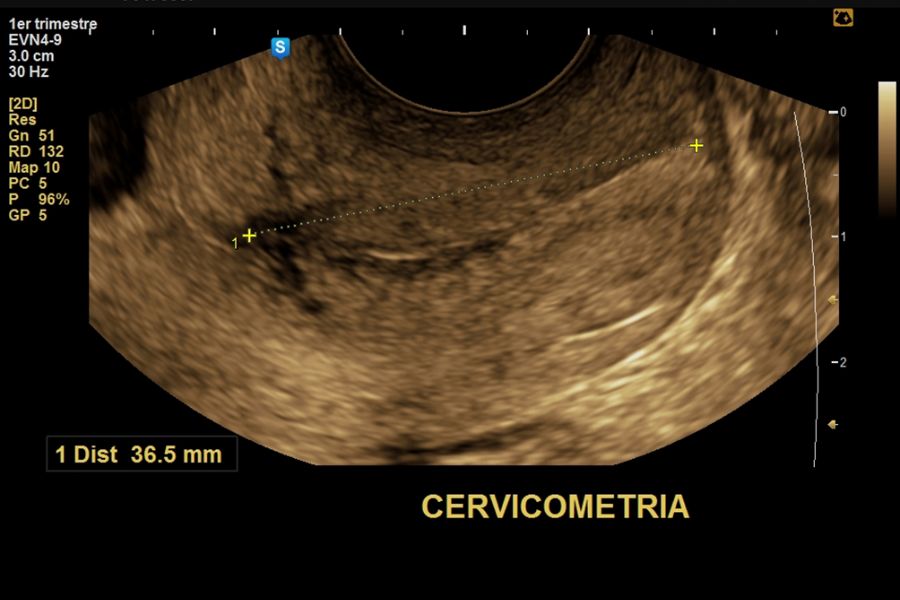

El momento óptimo para realizar el estudio ecográfico para cronicidad y animosidad es el 1er trimestre a partir de la semana 7, 11 a 14 con una sensibilidad > 98%, con una precisión menor pero aceptable en el segundo trimestre temprano (sensibilidad 90%).